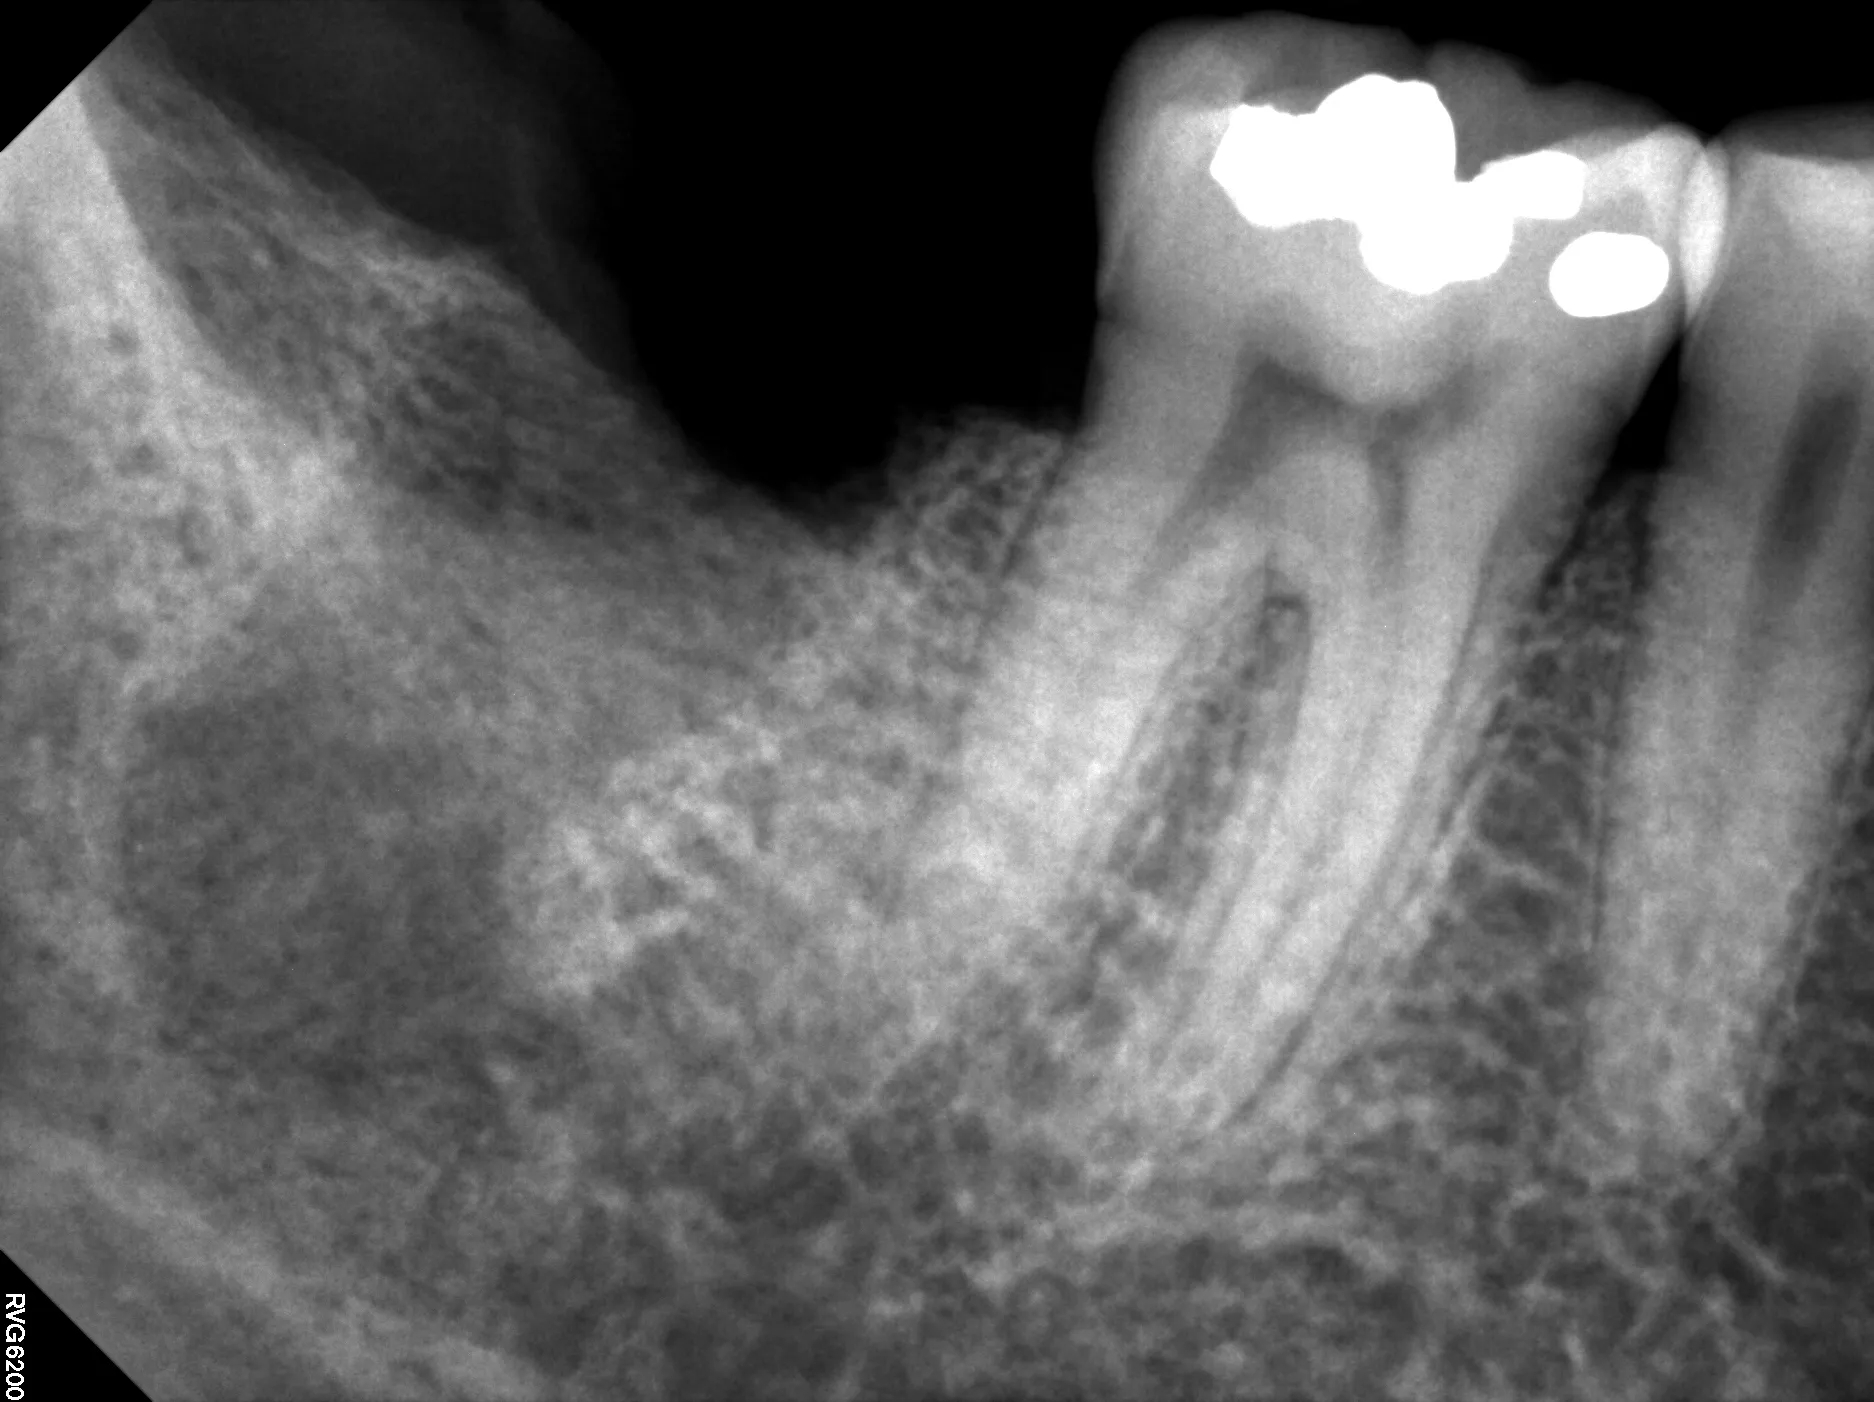

1. CBCT Imaging: Essential for evaluating root morphology, planning extraction approach, and identifying anatomical obstacles

Patient Outcome in This Case

At 12-month recall:

• Complete resolution of pain and periapical symptoms

• Radiographic evidence of bone regeneration around apical region

• CBCT confirms healing of periapical lesion

• Tooth asymptomatic to percussion and palpation

• Normal function—patient reports no limitations

• No evidence of root resorption